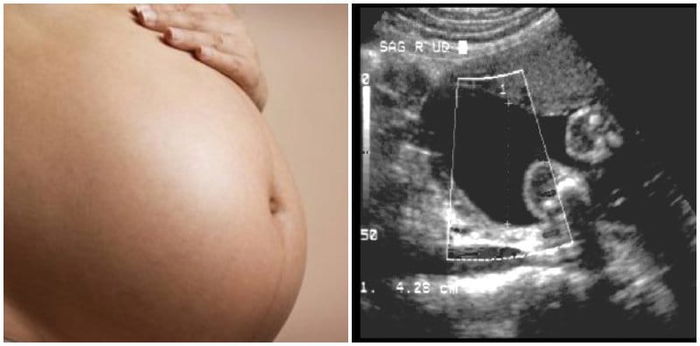

Pagsusuri para sa polyhydramnios sa pagbubuntis

Kung naghihinala ang duktor na mayroon kang polyhydramnios, siya ay magssagawa ng mas detalyadong ultrasound upang matantsa ang dami ng amniotic fluid sa uterus, at tignan kung mayroong fetal abnormalities.

Maaari rin isagawa ng duktor ang mga sumusunod na tests:

- Glucose challenge test (para sa gestational diabetes)

- Amniocentesis (sampling ng amniotic fluid para suriin kung may genetic abnormality o defect)

- Non-Stress Test (para matignan kung may abnormality sa tibok ng puso ng baby)

- Doppler ultrasound (mas malakas na ultrasound kung saan makikita ang circulatory system ng baby)